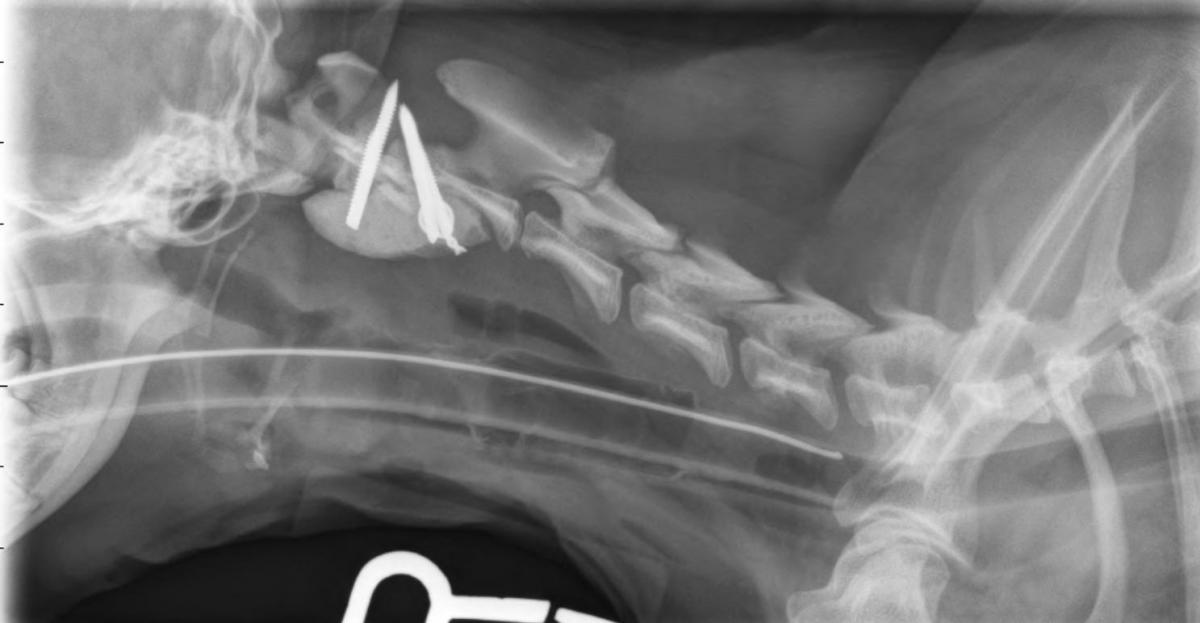

A. Atlantoaxial subluxation. The post-operative radiographs are shown below. Note the absence of the dens.